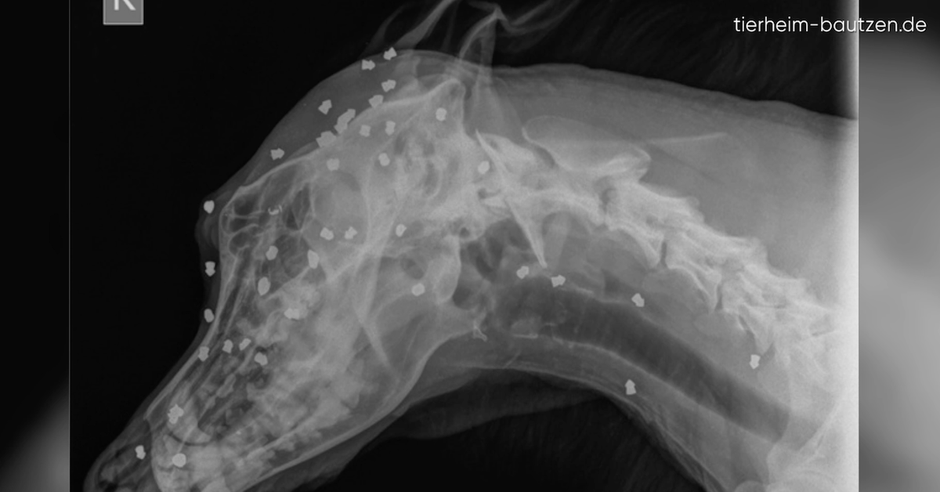

Hund überlebt 42 Kopfschüsse

Ein Röntgenbild aus Bautzen zeigt das unfassbare Leid eines Hundes...